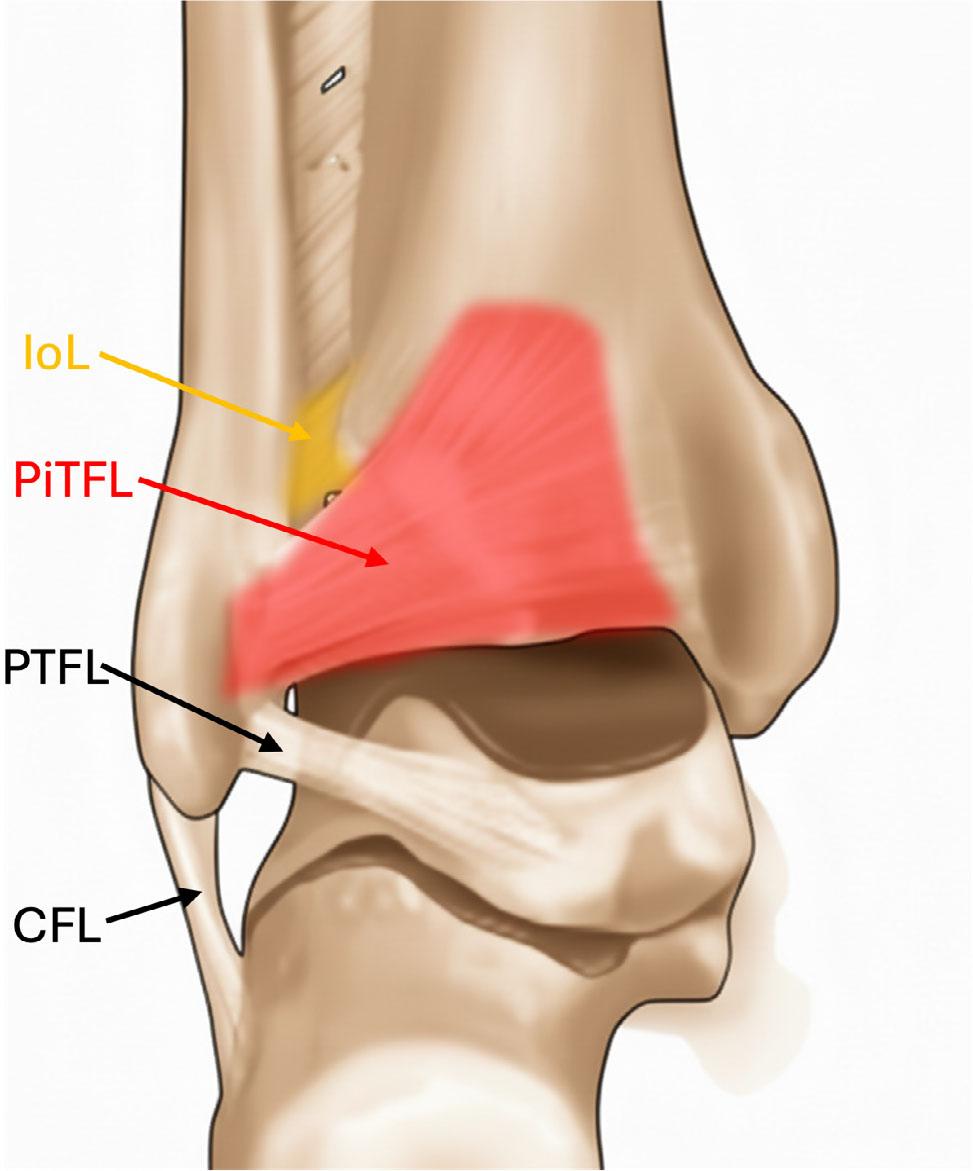

AiTFL – anterior inferior tibiofibular ligament; PiTFL – posterior inferior tibiofibular ligament; IoL – interosseous ligament; ATFL – anterior talofibular ligament; PTFL – posterior talofibular ligament; CFL – calcaneofibular ligament

The PiTFL is the strongest syndesmotic component, extending from the posterior tibial tubercle (Volkmann tubercle) to the posterior distal fibula (Fig. 2). It prevents posterior displacement of the fibula and contributes significantly to ankle mortise stability(6,7).

The interosseous ligament represents the distal thickening of the interosseous membrane (Fig. 2) and acts as a central stabilizer, transmitting load between the tibia and fibula, and maintaining their alignment during weight bearing(6,7).